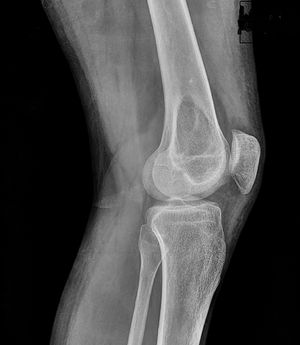

A 7-year-old male presented with pain after falling on an outstretched hand.